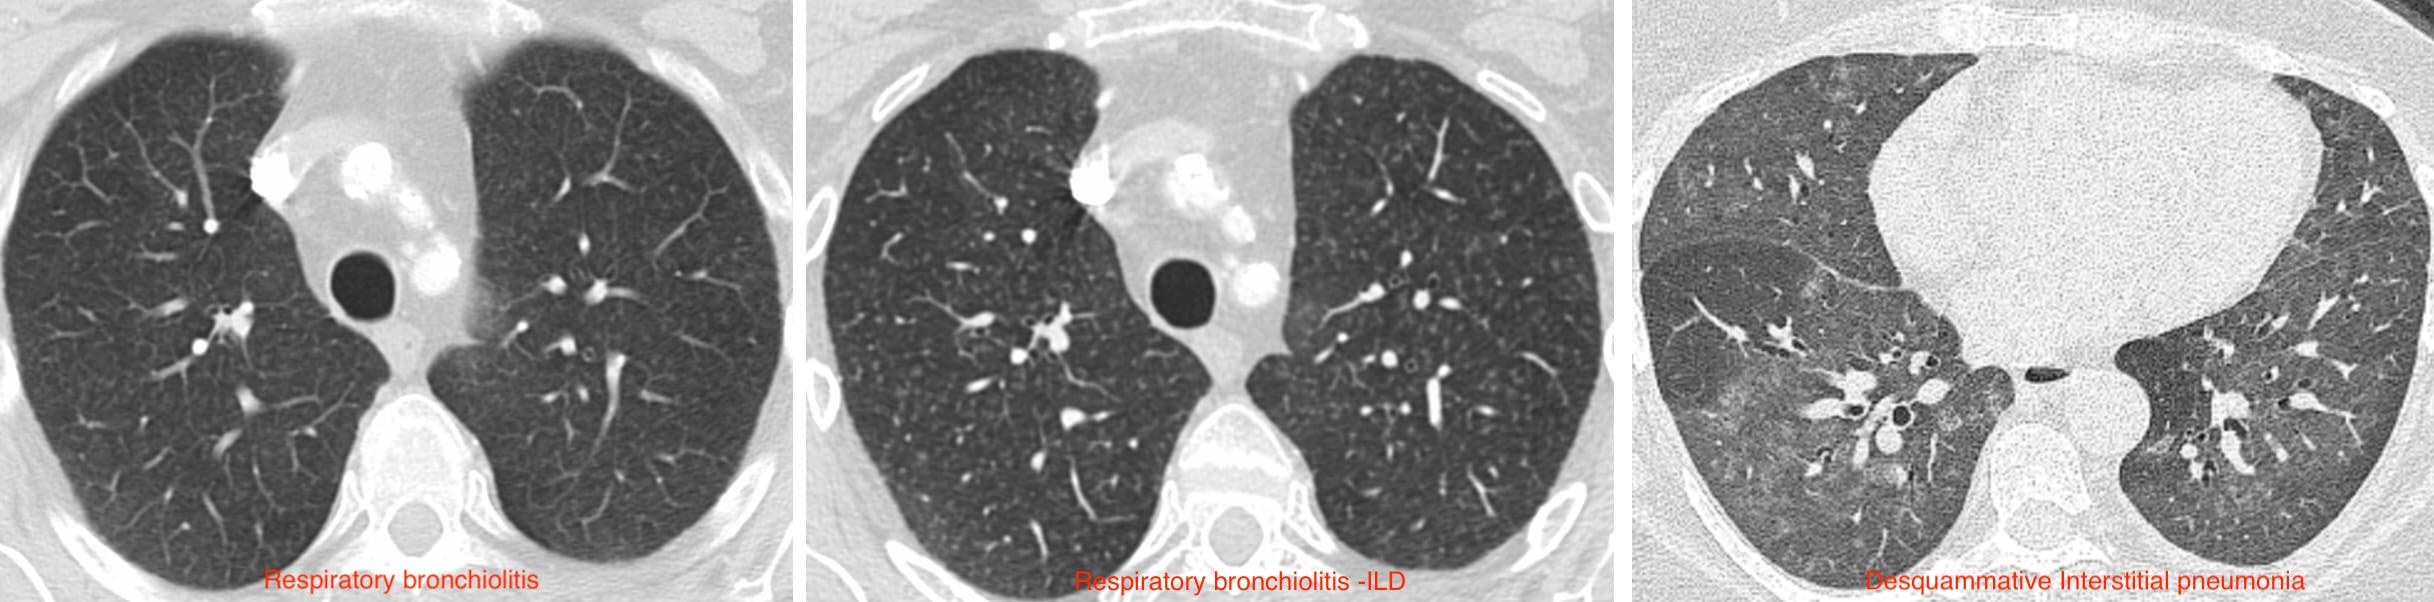

It’s a matter of how many I put there with my macrophage spray can…

Should we really discard DIP ?

Update of the International Multidisciplinary Classification of the Interstitial Pneumonias: An ERS/ATS Statement. Eur Respir J 2025; (https://doi.org/10.1183/13993003.00158-2025).

• Alveolar [Smoker’s] Macrophage Pneumonia (AMP) replaces Desquamative Interstitial Pneumonia

Finally! Why did it take so long ?